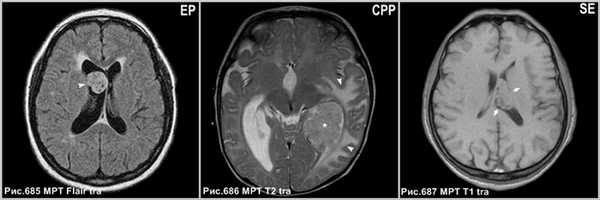

Субэпендимарная гигантоклеточная астроцитома (рис.688) встречается исключительно у пациентов с туберозным склерозом и интенсивно накапливают контраст.

Астроцитомы редко располагаются в желудочковой системе (рис.689).

Интравентрикулярные менингиомы (рис.690) имеют гомогенное контрастирование с определением чётких ровных контуров.

![central_neurocytoma_5]()

Субэпендимарная гигантоклеточная астроцитома с типичным расположением в области отверстия Монро (головка стрелки на рис.688). Астроцитома, растущая из прозрачной перегородки экзофитно в просвет правого и левого бокового желудочка (головка стрелки на рис.689). Внутрижелудочковая менингиома в центральном отделе левого бокового желудочка (звёздочка на рис.690), сопровождающаяся перифокальным вазогенным отёком прилежащего белого вещества перивентрикулярной зоны (головки стрелок на рис.690).